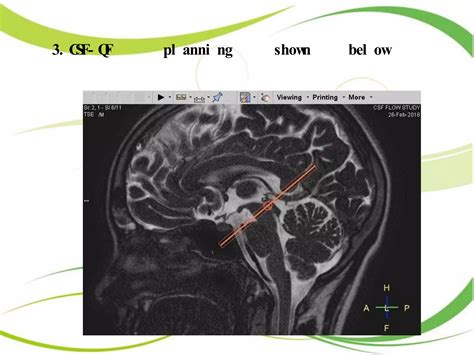

CSF Flow Study In MRI | PPTX

Cerebrospinal fluid flow MRI | CSF flow MRI protocol and planning